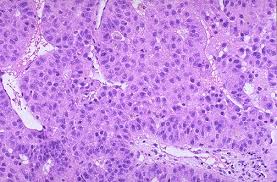

Afin d’approfondir cette question, les auteurs de cette publication ont effectué une étude cas-témoins afin de déterminer si l'obésité survenant au début de l’âge adulte affecte le risque, l'âge d'apparition, ou le devenir des patients atteints de CHC.

Cette étude suggère donc que l’obésité existant au début de l’âge adulte augmente le risque de développer un CHC à un âge précoce en l'absence des principaux autres facteurs de risque de CHC. En revanche, le pronostic n’est pas différent de celui des patients ayant un CHC d’autre origine.